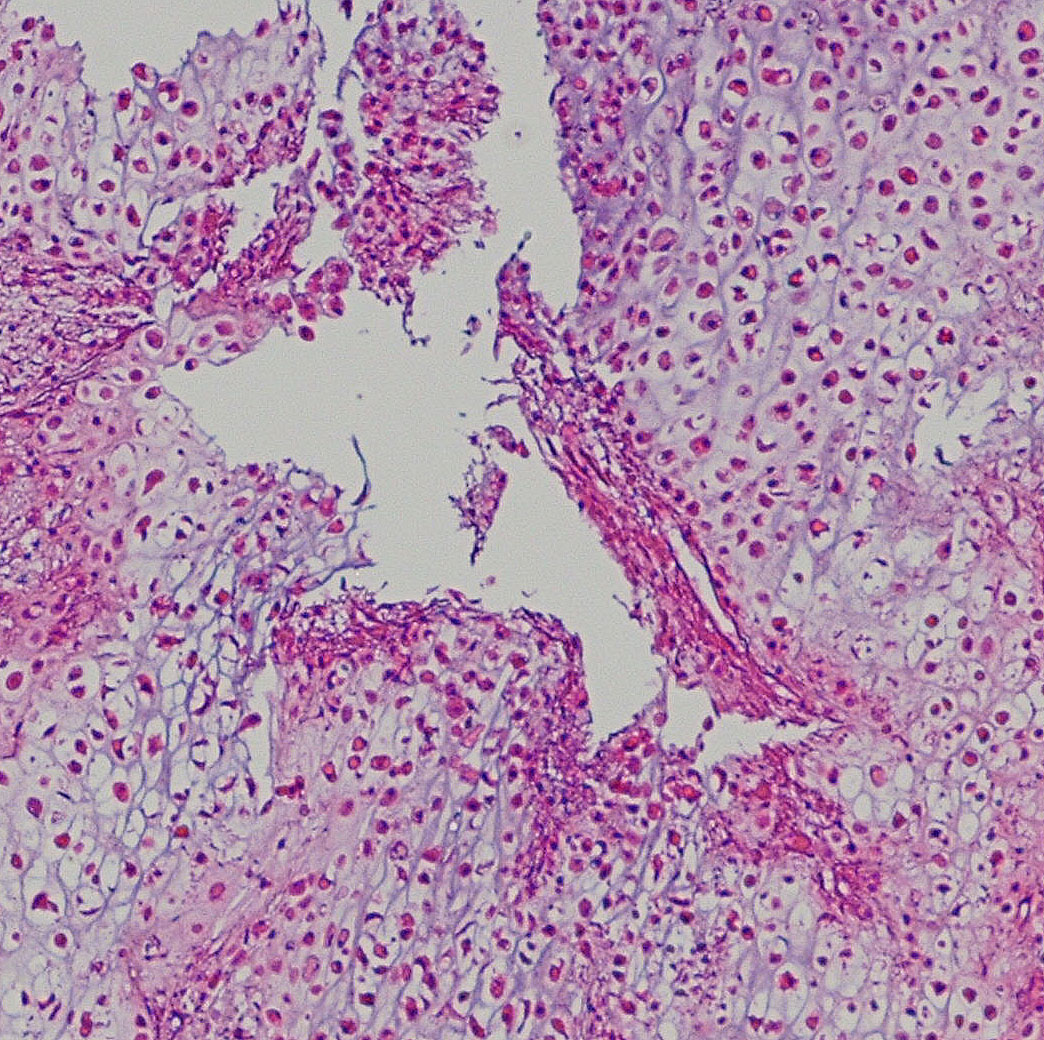

病理

低悪性度軟骨肉腫の病理像 grade 2 chondrosarcoma

背景は好塩基性の軟骨基質(粘液状 myxoid,軟骨様 chondroid)です。好酸性胞体をもつ異型紡錘形ないし上皮様細胞が多結節状に増殖しています。細胞密度はやや高い部分もあり,核は濃縮され大小不同や2核の細胞も見られます。MIB-1 index 3%